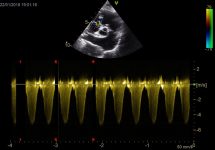

Haz clic en la imagen para obtener una vista más ampliada

Pregunta 2

En un paciente con enfermedad valvular degenerativa mitral, en estadio C con diagnóstico previo de edema pulmonar, tras el tratamiento con furosemida, su perfil de flujo transmitral previo mostraba una pseudonormalización, con una velocidad pico E de 1,1 m/s. En la revisión, este es ahora su perfil de flujo transmitral. ¿Qué está pasando? ¿Qué más podemos hacer por el paciente?

Existe una progresión de la patología hacia una disfunción diastólica restrictiva, con un aumento de la velocidad pico E hasta 1,76 m/s, lo que indica que el paciente es refractario al tratamiento. Posiblemente continúe con frecuencias respiratorias elevadas. Habría que reevaluar si existe resistencia a los diuréticos y trabajar en reducir la poscarga (presión arterial). Además, según la edad del paciente, podría ser candidato a cirugía mitral edge-to-edge (si cumple criterios anatómicos y funcionales) y, en caso de no ser idóneo, podría considerarse la septostomía auricular.